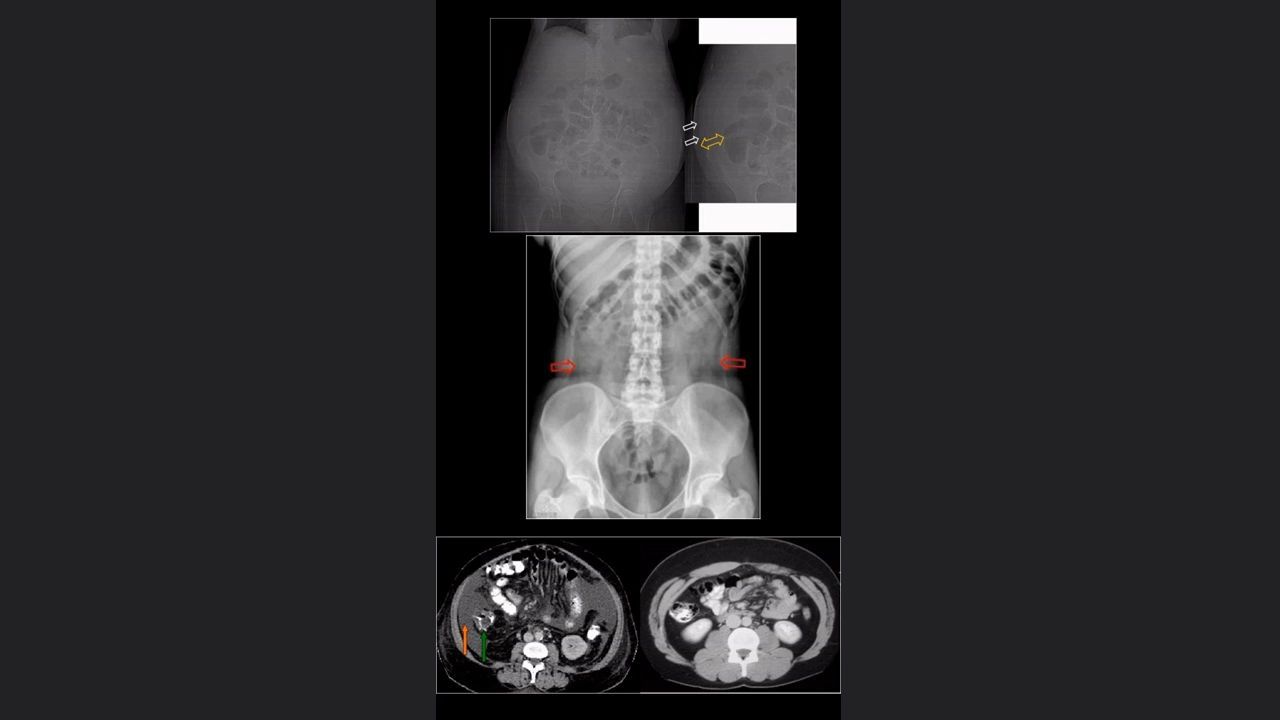

Pelvis y miembros inferiores

mediciones de la cadera